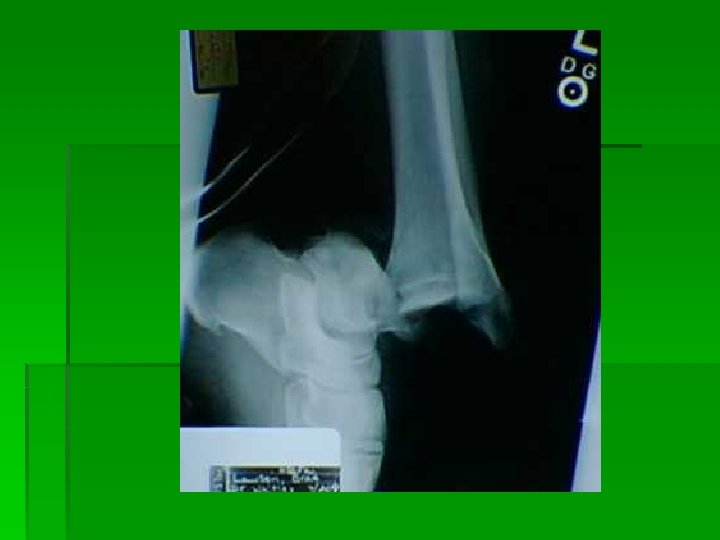

Ankle dislocation with no fractures. This takes a high degree of trauma and force. In this case this was generated as the result of a high flip off of a trampoline and impact with the ground. The ankle was in a plantar flexion and inverted position upon impact. This was an open dislocation.